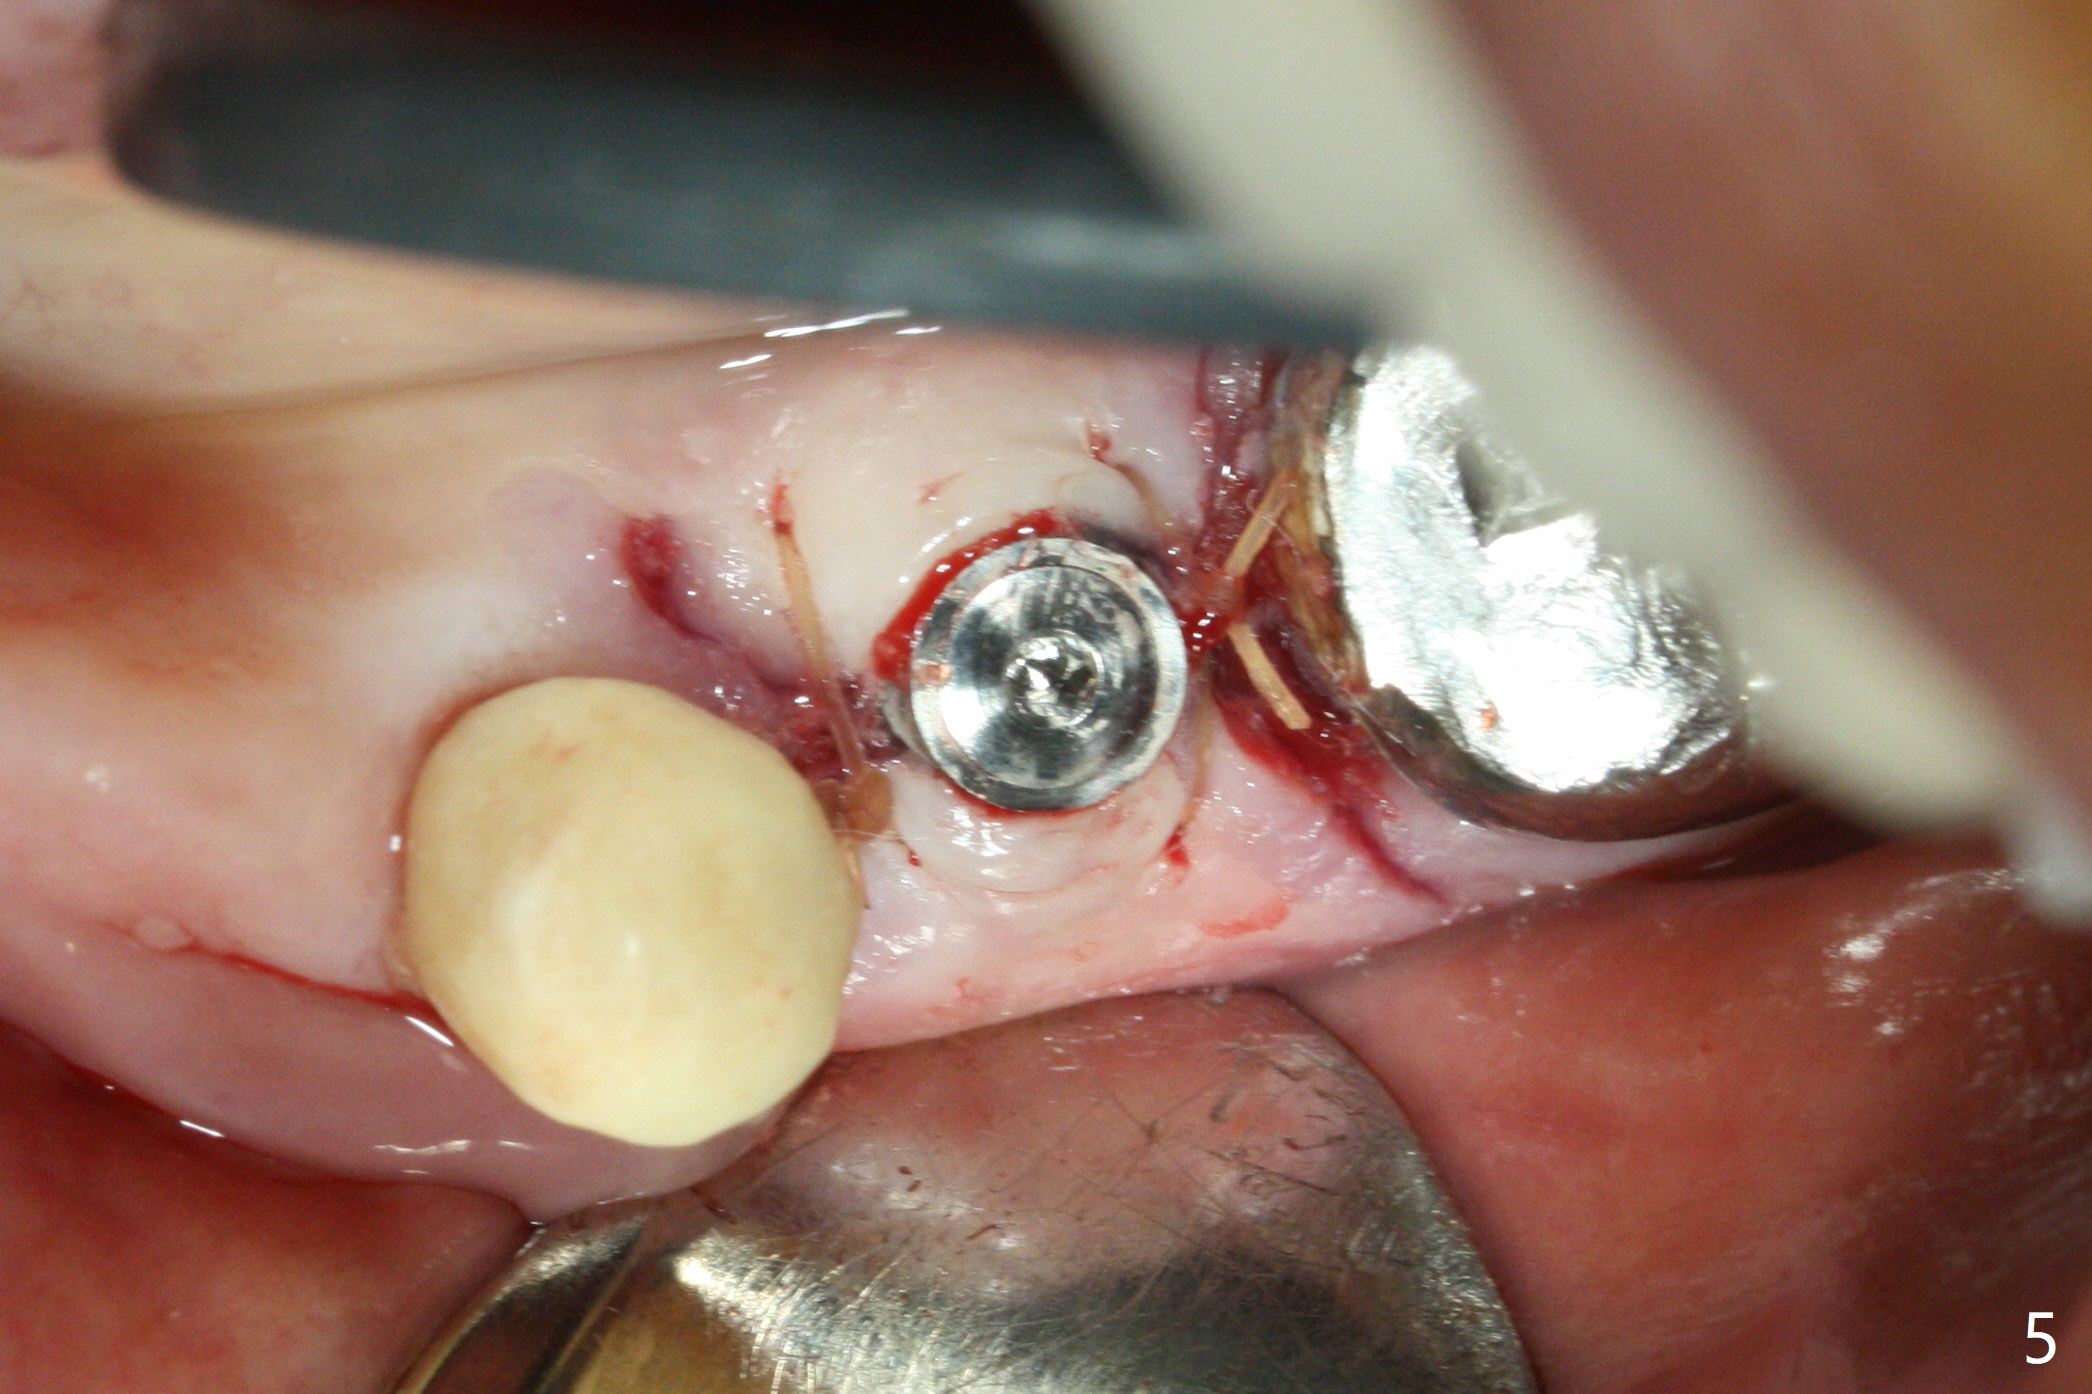

In fact the ridge at #19 is wide (Fig.1); there is enough bone to place a 5 mm implant (Fig.2 (5 mm implant positioner)). The gingiva is 3 mm in thickness. After use of Marking Drill, 5.3 mm Magic Drill (MD) for 9 mm and 4.8 mm MD for ~10 mm, a 5.5x9(3) mm Magicore is placed with primary stability, but too deep. When the implant is reversed, stability loses. After the autogenous bone from bone core is placed in the osteotomy, stability restores to a certain degree (Fig.3); there is no occlusal clearance when a 4.3x3 mm solid abutment is placed. Vera graft is placed around the implant (Fig.4 *) and a healing screw is placed (Fig.4,5).

There is no bone loss at #20 or 19 six and 3 months postop, respectively (Fig.6,7). After placing and trimming a 4.3x3 mm Magicore solid abutment, impression is taken (Fig.8). After cementation for #19 and 20 crowns, the crown of #20 is removed for cement removal; attention is paid to cement removal around the crown at #19. In fact, the removal is ineffective with the crown of #20 is reseated and retightened (Fig.9 >). Repeated removal proves to be futile (Fig.10 >). The most effective method will be to take X-ray immediately after #20 crown removal and reseating without torque so that it will be easier to remove the remaining cement if needed. It may be ok in term of hygiene, since proximal brush is used daily. While the crowns at #18 and 19 are being redone because of food impaction, the tooth #18 needs RCT; the Magicore seems to have no bone loss 4 months post cementation (Fig.11). CBCT shows that the Magicore seems to have been placed in the middle of the crest 7 months post cementation (Fig.12 (B: buccal)). The gingiva at #19 is apparently healthy 8 months post cementation. The crown at #19 is recemented 10.5 months post cementation (Fig.13).